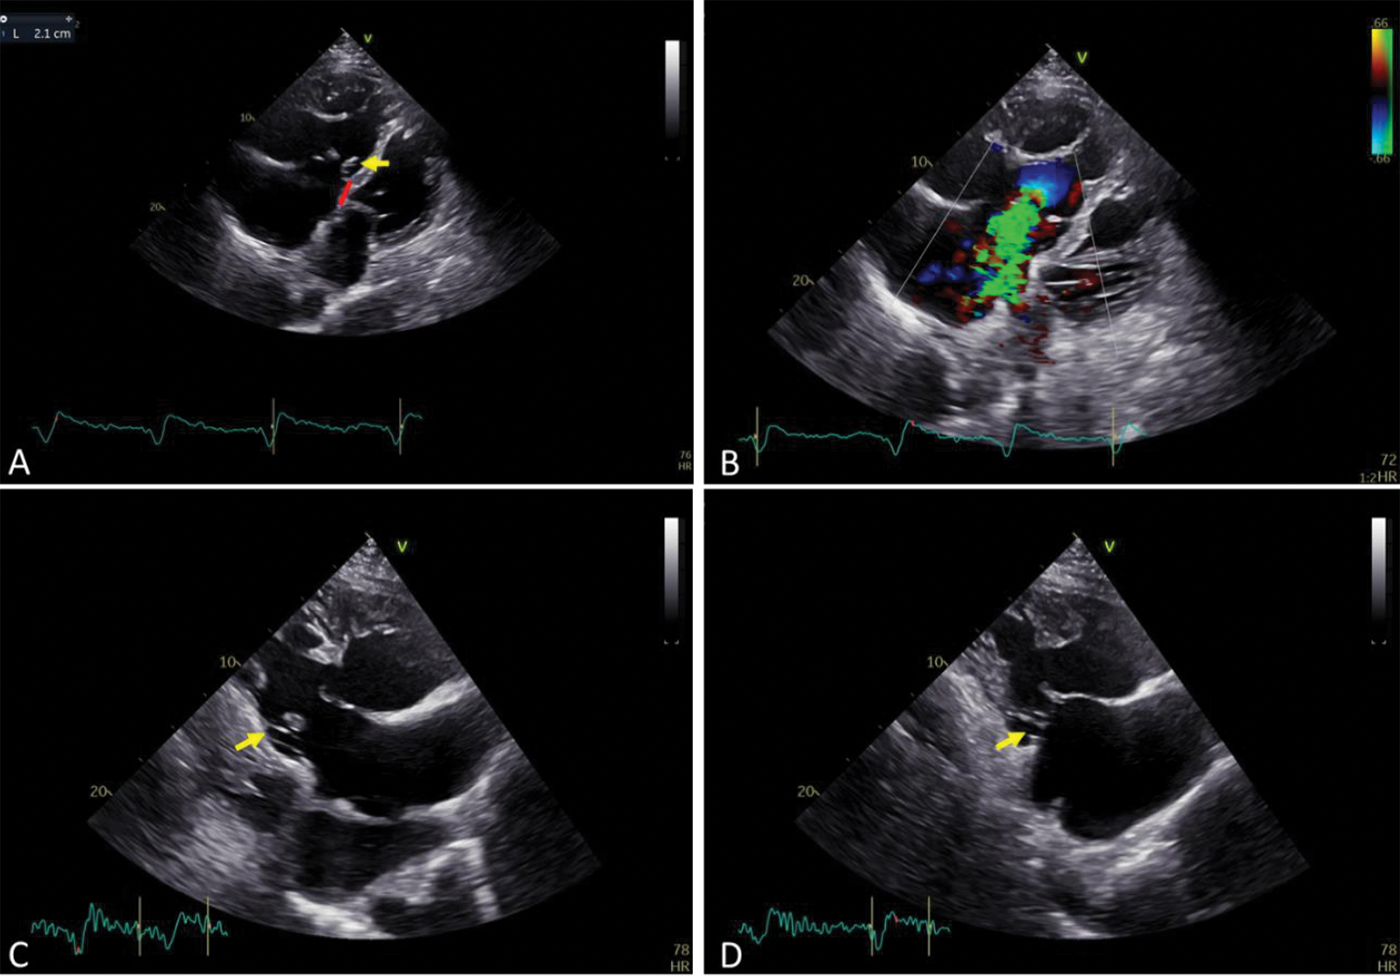

Figure 1: (A) Oblique apical four-chamber view (right lateral decubitus position)–septal leaflet hinge point apically displaced by 21 mm (9 mm/m2), incomplete delamination and tethering of the septal leaflet, yellow arrow–small septal leaflet and short chordae; (B) Severe tricuspid regurgitation due to coaptation gap; (C) Right ventricle inflow view–yellow arrow shows short chordae for septal leaflet; (D) Right ventricle inflow view–yellow arrow shows small but not apically displaced inferior leaflet